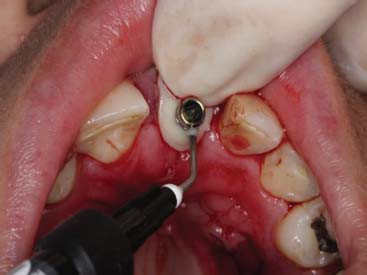

A paciente ERL, gênero feminino, 28 anos, procurou atendimento relatando dor na região anterior superior, com histórico de trauma prévio durante a mastigação. Na avaliação da paciente, o dente 21, aonde havia uma coroa cerâmica instalada com núcleo metálico, apresentava uma fratura obliqua, gengiva edemaciada, com sinais clínicos de infecção na parede vestibular do alvéolo (figura 1 e figura 2). O plano de tratamento incluiu a indicação de exodontia do dente 21, seguida de um implante imediato (Straumann® Bone Level SLActive) associado a um cicatrizador personalizado para manter a caracterização do contorno gengival do elemento.

Simultaneamente, foi realizada a exodontia do elemento 21, seguida da instalação do implante com toque final de 30N. O espaço alveolar remanescente foi preenchido primeiro com o enxerto de conjuntivo associado a uma membrana de colágeno reabsorvível (GenDerm – Baumer), juntamente com material de substituição óssea (Geistlich Bio-Oss, Geistlich Pharma) (figura 7 e figura 8).